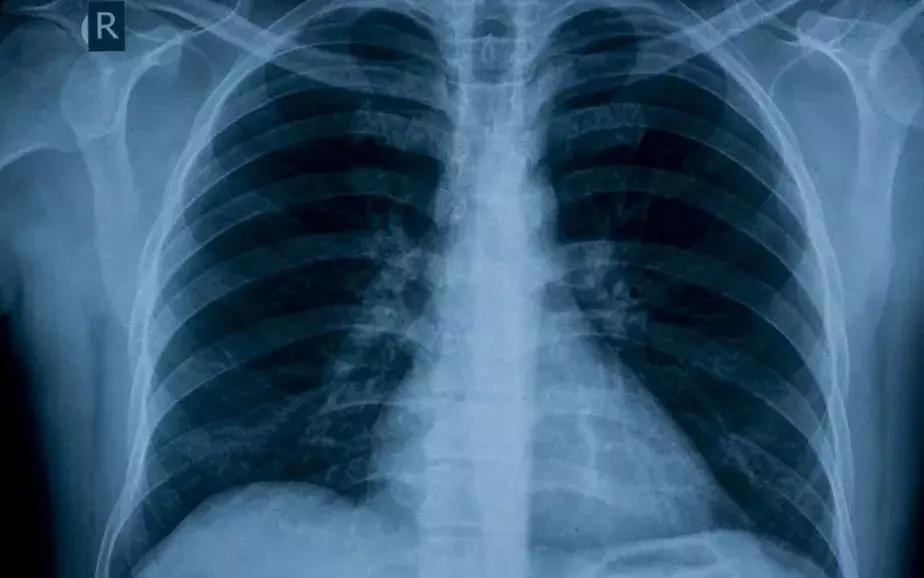

今天,全世界大概有10亿人患有高血压,到2025年这个数字可能会增加到15.6亿人。这意味着成年人中每四个人中就有一个患有高血压。高血压普遍存在于发展中国家以及发达国家。

长期缺乏控制或治疗不足的高血压是心脏病发作、中风、肾功能衰竭和其它心血管疾病发生的一个重大的风险因素。2004年的数据 (关于各个地区患有高血压人口的比例)显示了高血压患者惊人的两位数的增长。全球人口老龄化稳步上升和快节奏的生活方式,导致了不健康的饮食和运动的缺乏,过去五年增加的趋势预计将继续。

是的,不知不觉中,高血压,已成为全世界老年人的头号生命杀手。因此,降压药则顺理成章地成为了高血压患者的救命稻草,有时候,一粒降压药可以遏制住肆无忌惮的血压,可以挽救一个濒临无望的生命。